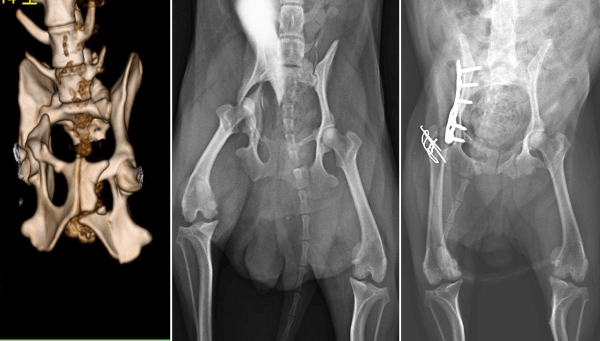

多発性骨折

(右腸骨体骨折、左坐骨及び恥骨骨折、右肘関節脱臼、右股関節脱臼、両側下顎体骨折)

チワワ

9歳齢

3.25 kg

骨盤骨折 大転子骨切り術、ロッキングプレートによる整復固定

肘関節脱臼 非観血的整復

両側下顎体骨折 ラグスクリュー法、サークラージワイヤー法

左:術前 CT

真ん中:術前レントゲン

右:術後レントゲン